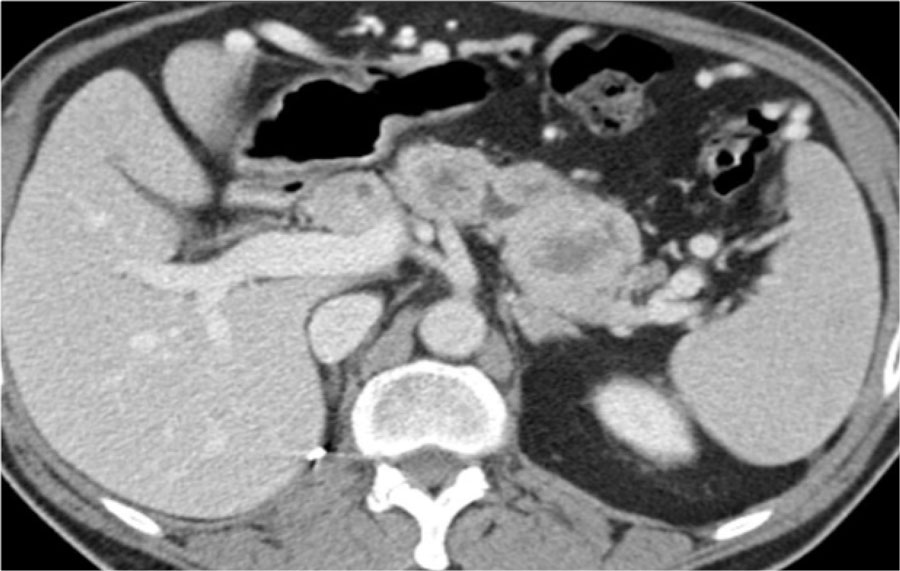

Когорта FUSCC

Предоперационная оценка пациентов включала; медицинский осмотр, рутинные анализы крови, электрокардиография, проверка функции легких и компьютерная томография (КТ) органов грудной клетки. Все пациенты были оперированы одной и той же хирургической бригадой посредством латеральной мышечно-сохраняющей или подмышечной торакотомии и селективной интубации с вытеснением воздухом резецируемого легкого. При возможности выполняли клиновидную резекцию легкого с широкими свободными от опухоли краями; лобэктомию проводили только при центральном или большом поражении.Таргетная терапия, лучевая терапия и традиционная химиотерапия были зарезервированы только для пациентов, не пригодных для хирургического вмешательства или нерезектабельного метастатического заболевания. Время, прошедшее между первой метастазэктомией и смертью (или последним последующим наблюдением), считалось выживаемостью.